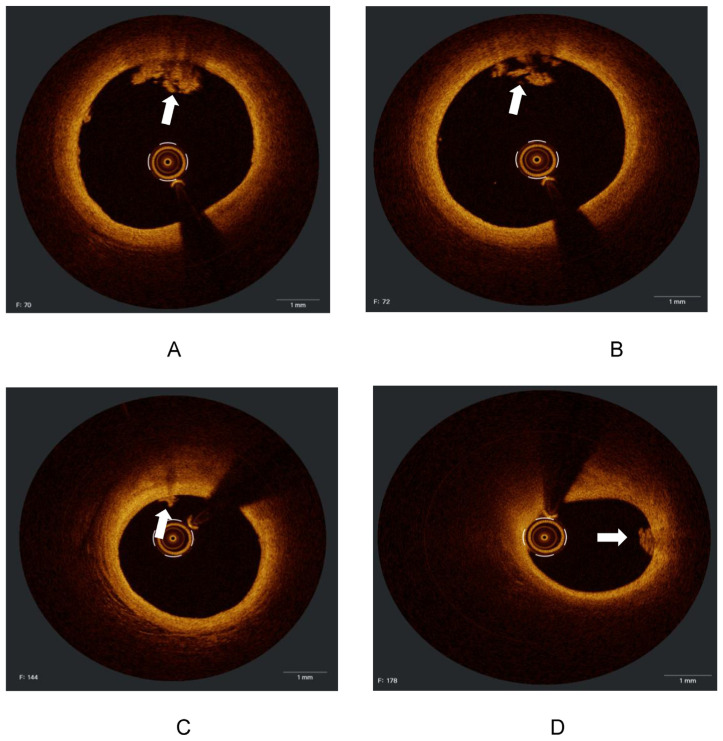

Abstract Image